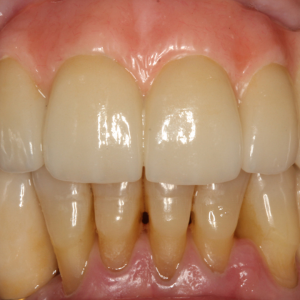

La estabilidad del hueso marginal y del tejido blando alrededor de los implantes dentales se ha establecido como la principal característica para asegurar la salud del implante.La condición...

La integración del tejido blando periimplantario sigue siendo fundamental para el éxito a largo plazo de la terapia con implantes. La formación de una barrera temprana y duradera para proteger las...